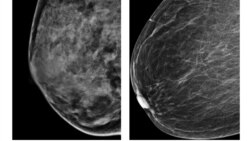

Ko’krak saratonining turli shakllari va bosqichlari bor